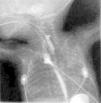

En los días siguientes, el cuadro respiratorio empeoró, apareció un enfisema subcutáneo con aparición de un enfisema intersticial en la radiografía de tórax (fig. 1), y se instauró ventilación de alta frecuencia. Posteriormente, pudo pasar de nuevo a VMC, y fue extubado 24 h después, aplicándose presión positiva continua en la vía aérea por vía nasal (n-CPAP). El neumomediastino persistió sin neumotórax asociado.

Figura 1. Radiografía de tórax y abdomen. Se observa la existencia de un neumomediastino con enfisema intersticial y enfisema subcutáneo en la faringe.